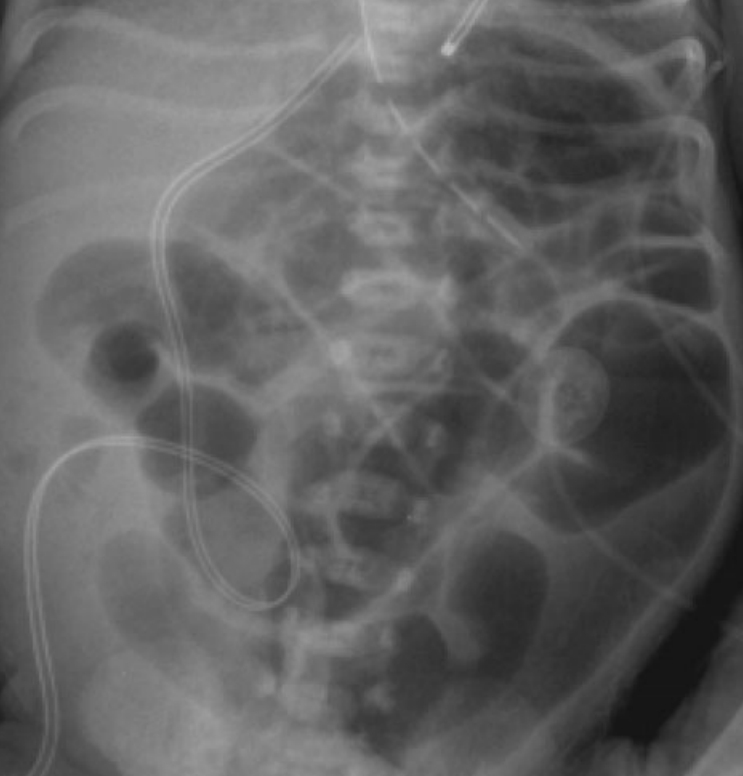

diagnosis: x-ray show transition point and gas filled plug. Echogenic bowel on prenatal ultrasound can be an early hint.

Step 1: xray. Bad colon normal. Good colon dilated

90%: contrast enema to see transition point